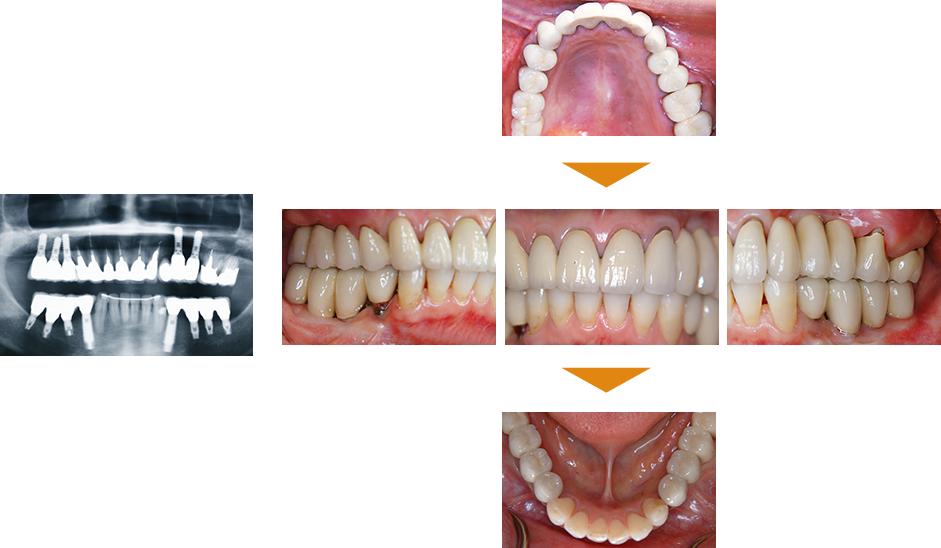

症例4

その他の即日荷重インプラント

|

| 治療期間 | 約4カ月 |

|---|

| 費用 | 下顎 5,170,000円(税込) |

|---|

※状態により、骨補填等別途で費用が発生する場合もございます。